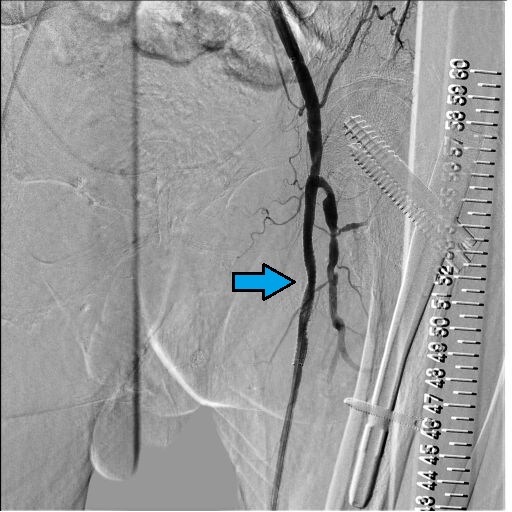

図10.BK Post画像

造影遅延なく良好な血流が確保されている。